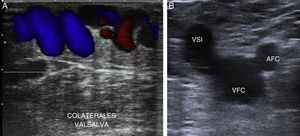

Los shunts venovenosos se pueden activar durante la relajación o contracción muscular y deben diferenciarse de otras patologías que pueden manifestarse de forma similar. Un claro ejemplo es el shunt vicariante o shunt de circulación colateral10, que ocurre en un paciente con una trombosis venosa aguda o un síndrome posflebítico no recanalizado y mal colateralizado, que puede desarrollar un cuadro de hipertensión venosa sin reflujo. Se crean para compensar un obstáculo del SVP, y el SVS actúa como puente o colateral para el retorno sanguíneo; tiene una actividad continua en sístole (contracción) y diástole (relajación muscular).

En segundo lugar, con el paciente en decúbito supino valoraremos el SVP desde la VFC hasta la poplítea y bifurcación de los troncos tibioperoneos, con el fin de asegurar la permeabilidad y competencia del mismo19.

Es importante analizar la morfología de la onda espectral con Doppler pulsado a nivel de la VFC, que debe ser fásica y modificarse con la respiración, con el fin de descartar una posible obstrucción proximal en el eje ilíaco. Descartaremos así que el reflujo en la safena interna sea debido a un flujo vicariante2,10.

La existencia de reflujo en la vena femoral común y en la poplítea debe valorarse unos centímetros por encima de la unión safenofemoral o safenopoplítea.